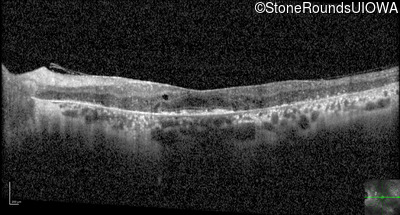

Optical Coherence Tomography - Right - 20/25

Exemplar / OCT Stack

Optical Coherence Tomography - Left - 20/70 +1